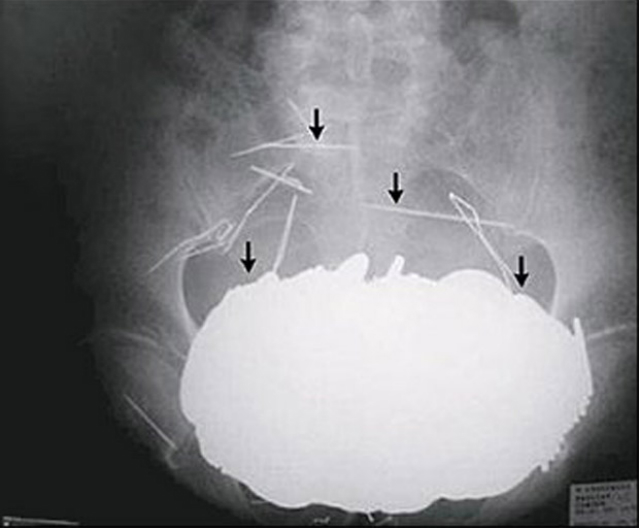

Incluso la policía le mandó sacar una radiografía para ver la sortija y acá está: